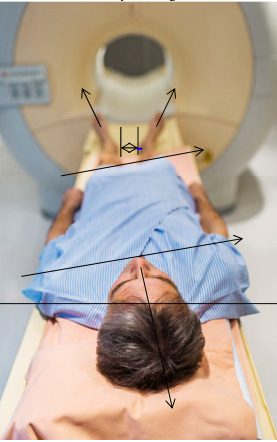

MRI- Röntgen-Bilder etc.

Fehlen die Abweichungen aus der Körper-statischen Mittellinie mit den Messdaten, damit man weiss, wie diese Abbildung zustande kam.

Abbildung:

Ohne reproduzierbare Anhaltspunkte bezüglich Fussstellung und den Ausweichhaltungen wird eine Person in der entspannten Körperhaltung bebildert.

Was kann man aus so einem Bild lesen.

Leider fehlen die erwähnten Angaben,

damit ein aussagekräftiges und reproduzierbares Bild entsteht, das Ursachen bezogen Auskunft gibt.

Was kann eine solche Aufnahme ohne Muskelspannung aufzeigen?

Über die Knieentlastung verändern sich Hüftgelenk- und Rückgrat-Stellungen.

Wie kann somit eine Stellungsveränderung z.B. über eine einseitige Knieblockade, oder eine Stellungsveränderung der Beinschenkelwinkel zum Becken, eine schiefe Beckenebene festgestellt werden, die eventuell Gelenk oder Rückenbeschwerden verursachen können. Weiter verändert sich die Rückgrat-Stellung. Wie werden dabei Hohl- und Flachrücken im Zusammenhang beurteilt?

Knie-Unterlage zur Entlastung

Fussstellungen verändern Gelenkstellung im Becken

Kopf-Unterlage verändert die Oberkörperspannung.

Ein Körper ohne Belastung stellt wohl ein optisch genaues Bild dar, kann jedoch keine Auskunft über einen fehlbelasteten Körper geben.